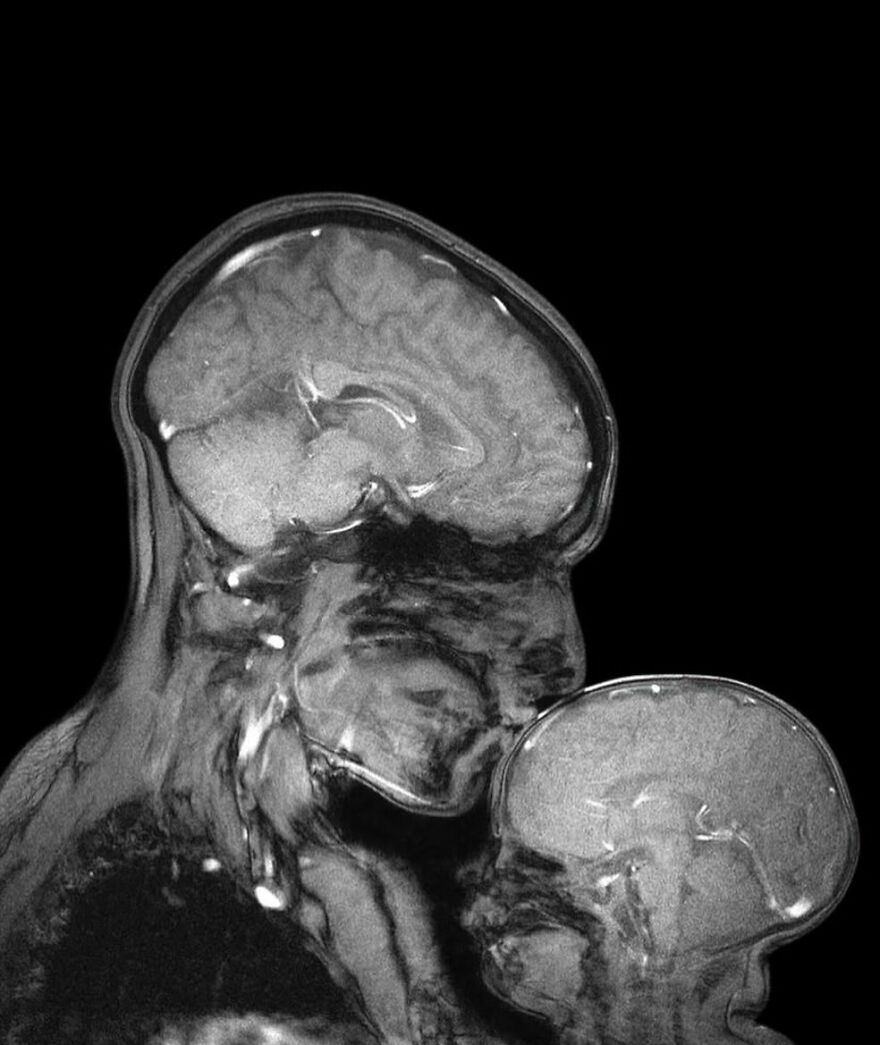

Man's severed hand attached to his ankle to keep it alive until the arm is healed enough for reattachment